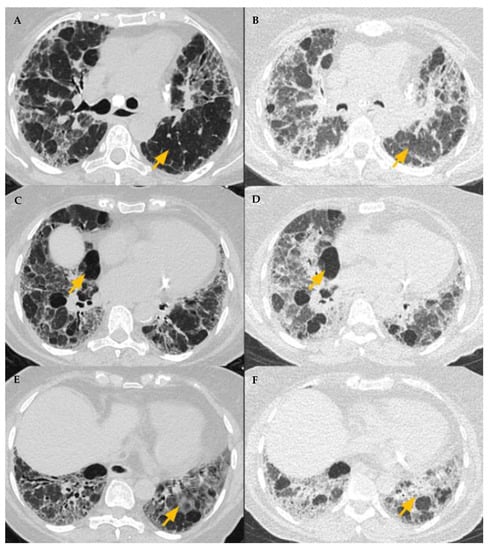

Three categories of NFHP (Table 3, Figure 8) and FHP (Table 4, Figure 9, Figure 10, Figure 11 and Figure 12) have been described.

Figure 9. Typical fibrotic HP. Baseline CT (A) shows patchy GGOs. Follow up CT 3 years later (BD) shows traction bronchiectasis (curved arrow), reticulations, patchy GGOs, and consolidations. Random axial and craniocaudal distribution of fibrosis. Axial inspiratory (C) and expiratory phase (D) shows three-density sign with expected increased attenuation of normal lung (short arrows) and GGOs (black asterisk). Lucent areas of decreased attenuation and vascularity depict air trapping (long arrow).